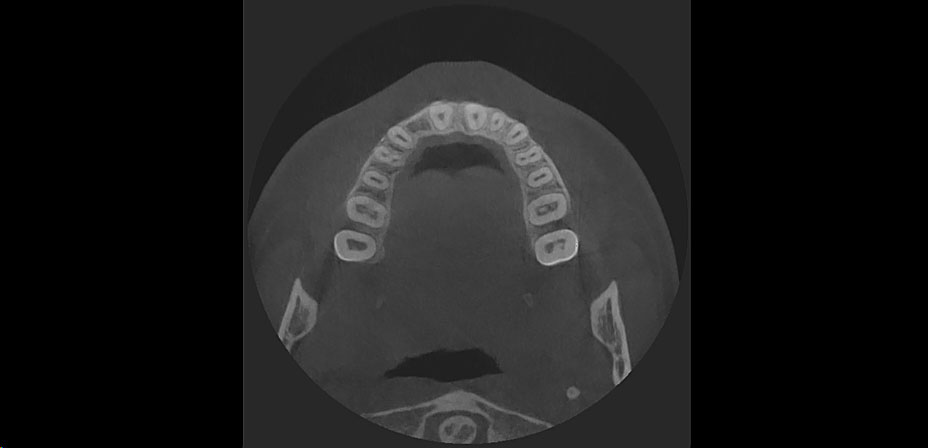

Schonende und punktgenaue 3D-Bilder

Wir nutzen in unserer Praxis die neuesten Stand der Röntgentechnologie: die Digitale Volumentomographie. Sie bietet mit aufschlussreichen 3D-Bildern wesentlich genauere Informationen als bisher. Mit der Volumentomographie lässt sich die Röntgen- Bestrahlung auf extrem kleine Untersuchungsfelder begrenzen. Die Aufnahmezeit ist außerordentlich kurz, die Strahlenbelastung wird deutlich minimiert. Auch auf eine aufwändige Computertomografie in der “Röhre” kann nun verzichtet werden. In vielen Situationen hilft uns die dreidimensionale Röntgenaufnahme also erheblich weiter.

+ Mithilfe der aussagekräftigen 3-D Bilder können wir das Knochenangebot wesentlich genauer einschätzen